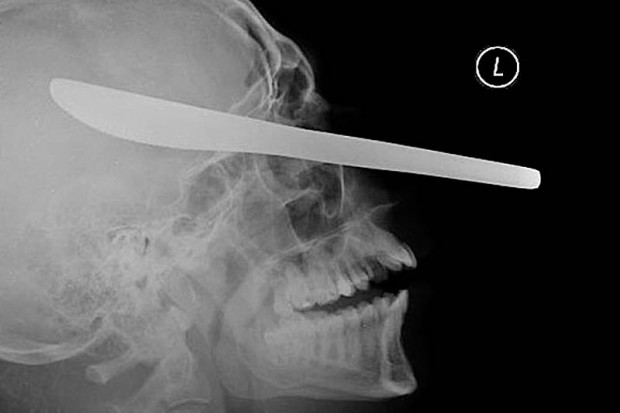

19. Нож для резки масла в глазу пациента.